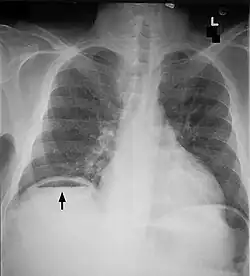

Röntgenuntersuchung

Die radiologische Untersuchung des Bauches – meist eine einfache Leeraufnahme des Abdomens ohne Kontrastmittel im Stehen oder in Linksseitenlage – kann freie Luft (als Zeichen einer Hohlorganperforation) und/oder das Vorliegen eines Darmstillstandes zeigen. Eine Computertomografie oder Magnetresonanztomographie kann zusätzlich Hinweise auf die Ursache der Peritonitis geben.